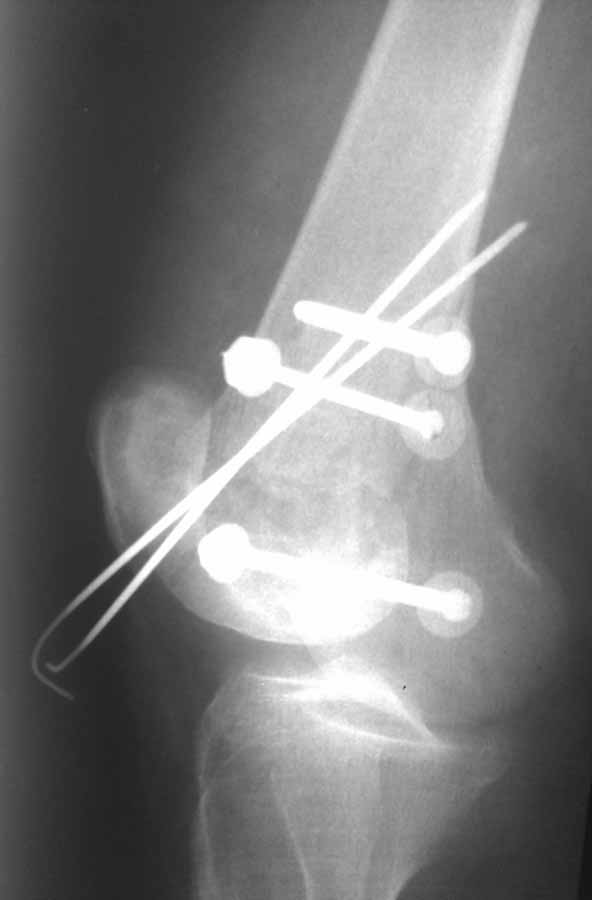

Коллеги, извиняюсь за задержку с результатом. Через медиальную артротомию обнажили н/3 бедра, отрепонировали внутренний мыщелок, затем по нему сопоставили суставную поверхность бедра с латеральным мыщелком.

Больная выписана в ортезе с регулируемым углом сгибания в колене, с рекомендациями через 3 нед. удалить спицы и начать разрабатывать сустав.

По прямому снимку репозиция удалось, поздравляю! А с латеральной стороны подозрение на флексионный компонент латерального мыщелка остается, а снимок получился косым, надо было бы повторить.

Выбор имплантов не совсем удачный, подкожно выступающие болты в мыщелках вскоре могут привести к проблемам. Вместо солитарной фиксации болтом-стяжкой дистально можно было бы добавить пару винтов, которые создали бы ротационную стабильность и межфрагментарную компрессию.

Возможно, есть скрытый замысел, неочевидный для нас - не понятны латерально оставленные спицы. Спицы возможный очаг вторичного осложнения, и, тем более у взрослых, тонкие спицы не создают адекватную фиксацию.

Djoldas,скрытого смысла в спицах нет. Без них латеральный мыщелок получается фиксированным только к медиальному, который, в свою очередь, фиксирован к проксимальному отломку. Соответственно латеральный мыщелок не фиксирован к бедру. Спицами мы попытались создать какую-никакую-стабильность латерального мыщелка относительно проксимального отломка бедра.

Болт-стяжка, на мой взгляд, создает не меньшую межфрагментарную компрессию чем винты. Не понял относительно ротационной стабильности винтов.